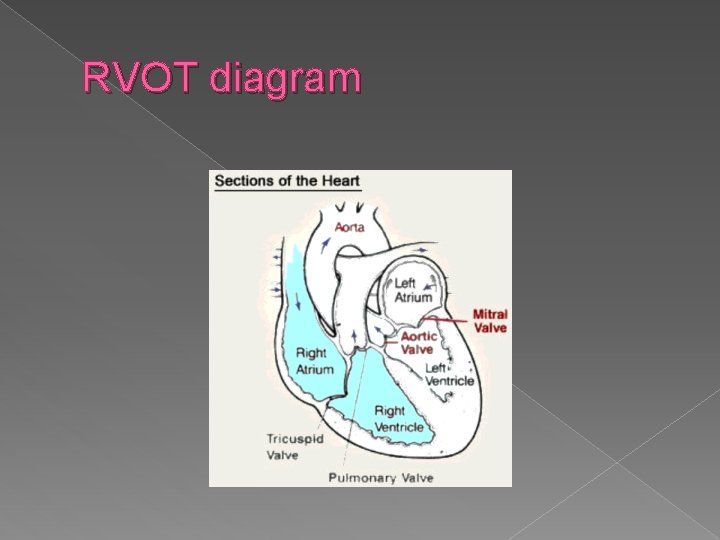

Right ventricular outflow tract view (RVOT) › ID the origin of pulmonary trunk from the right ventricle › Correct orientation of pulmonary trunk is draping anterior to the aorta when seen in cross section. › Diameter of the pulmonary artery is 9% larger than that of the aorta

RVOT diagram